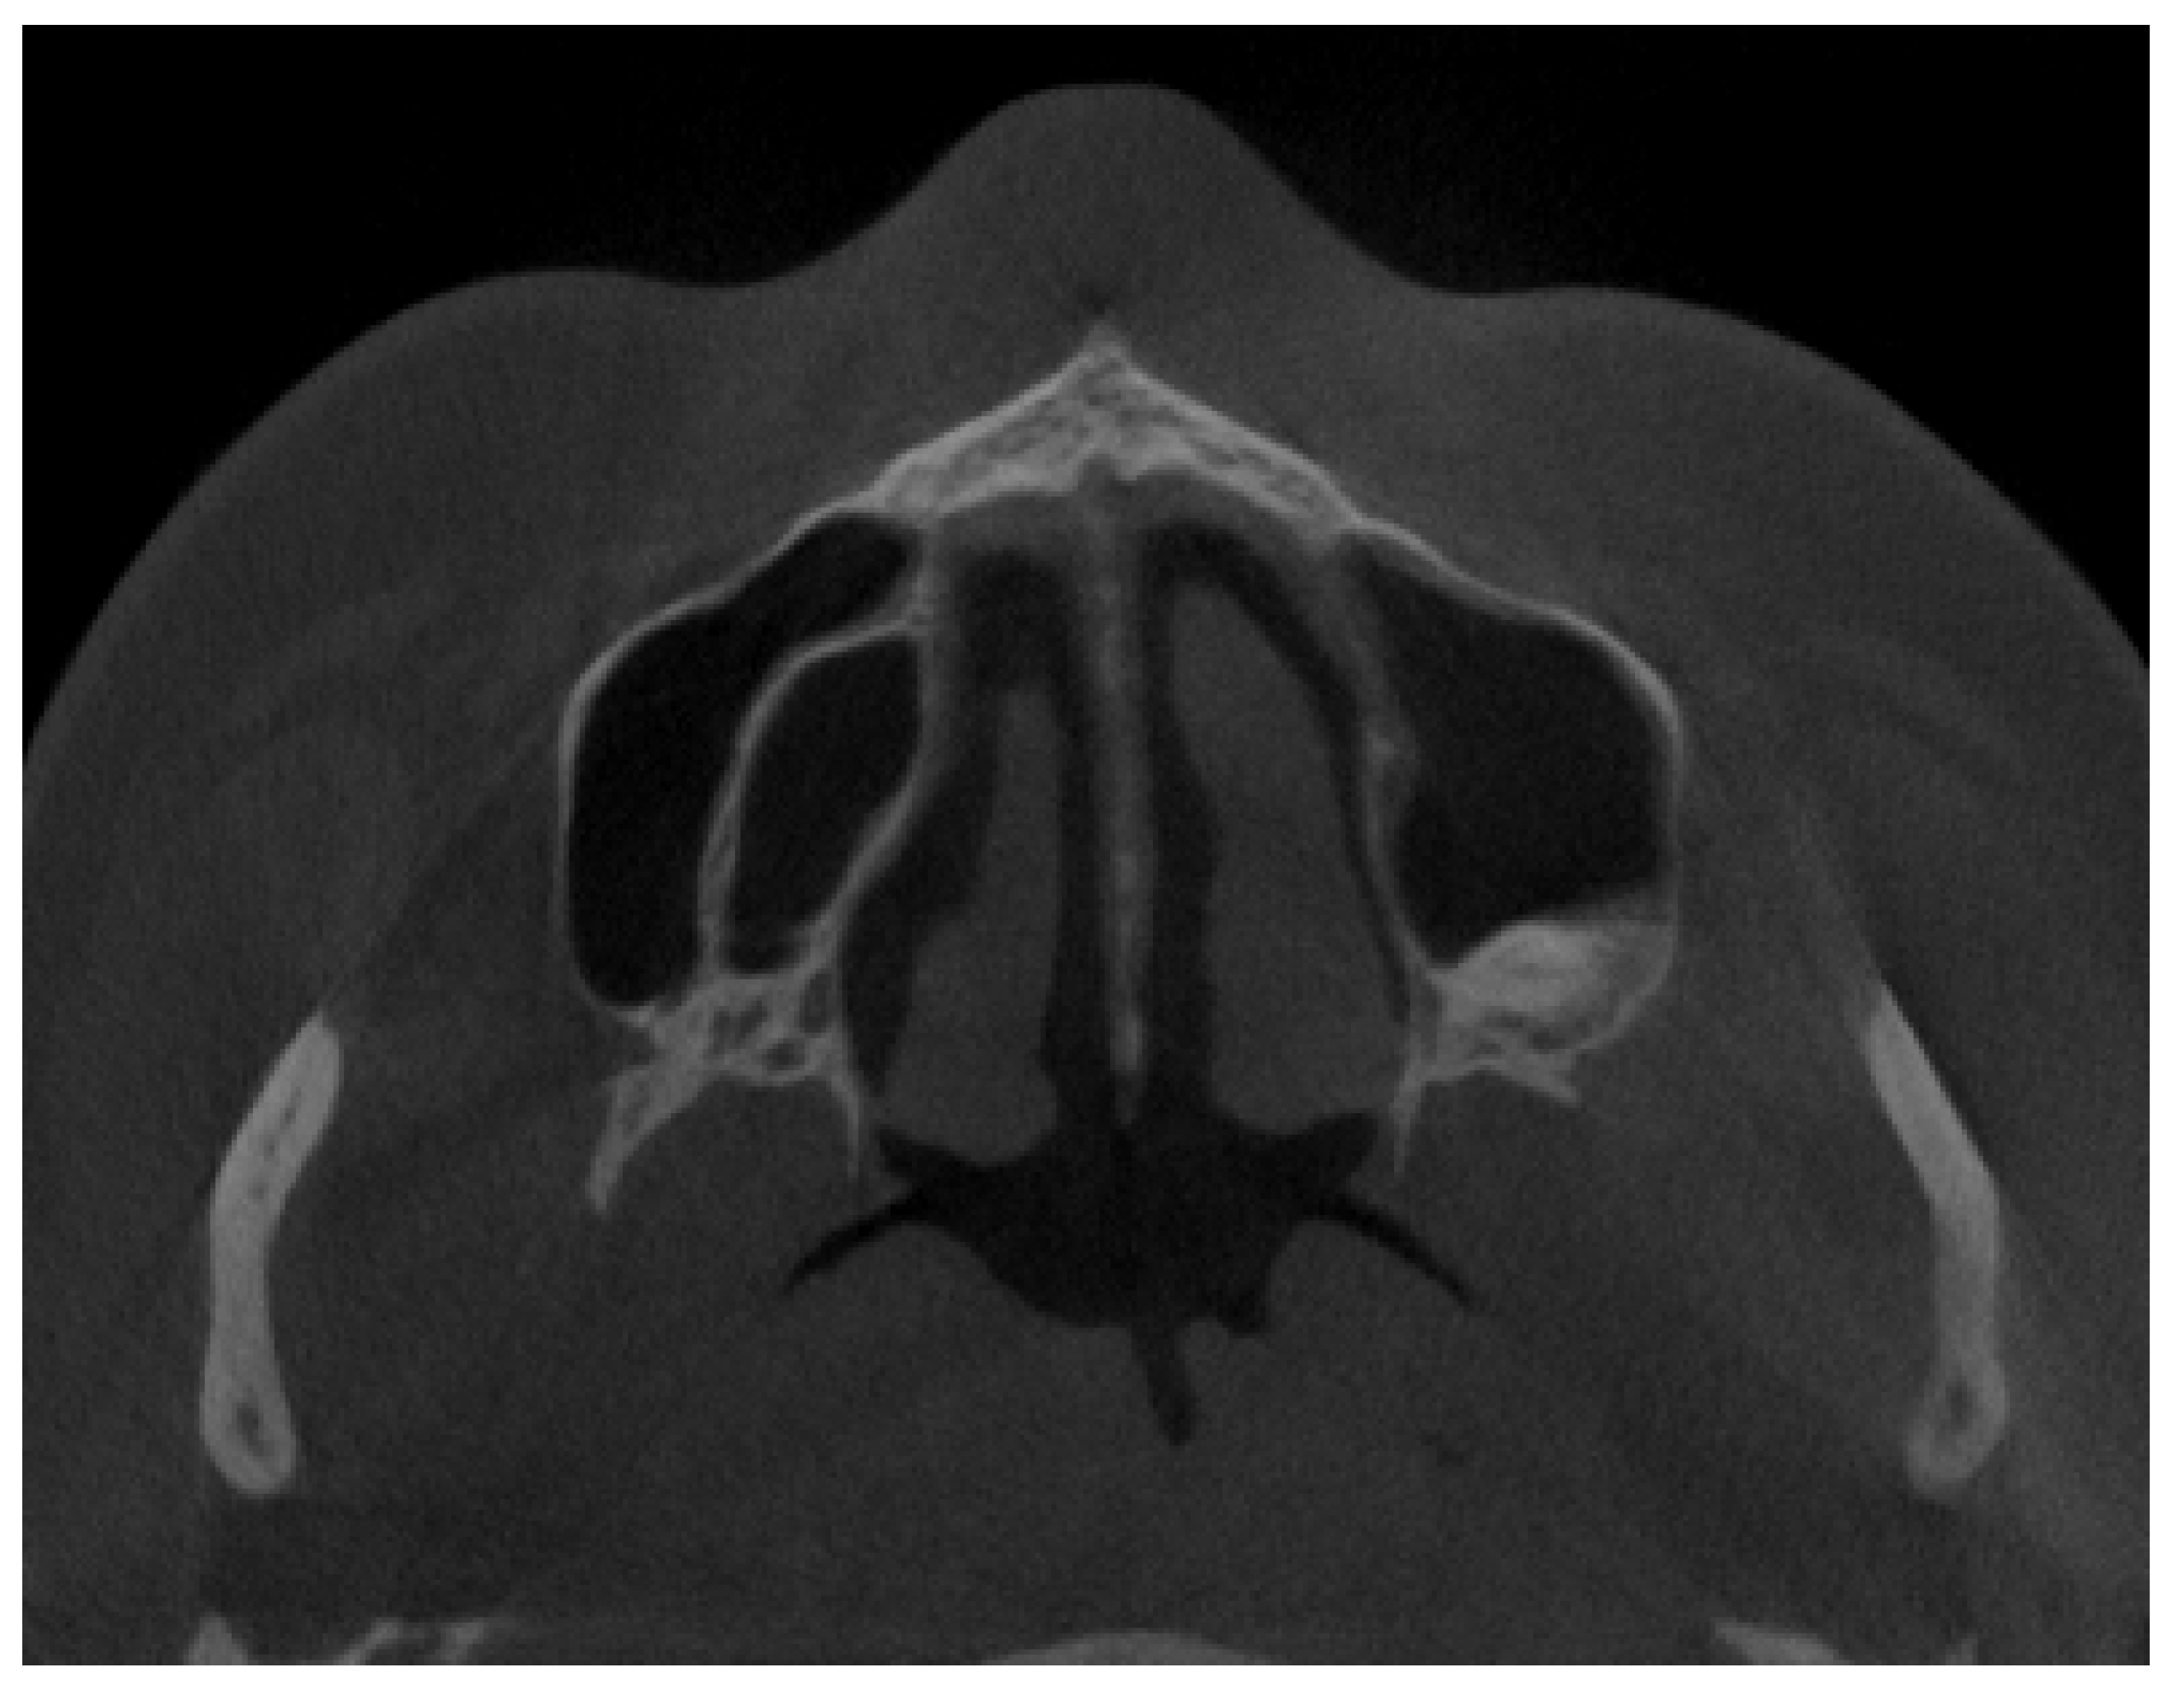

2.3. Methods—Classification Proposal

3.2. Classification Proposal